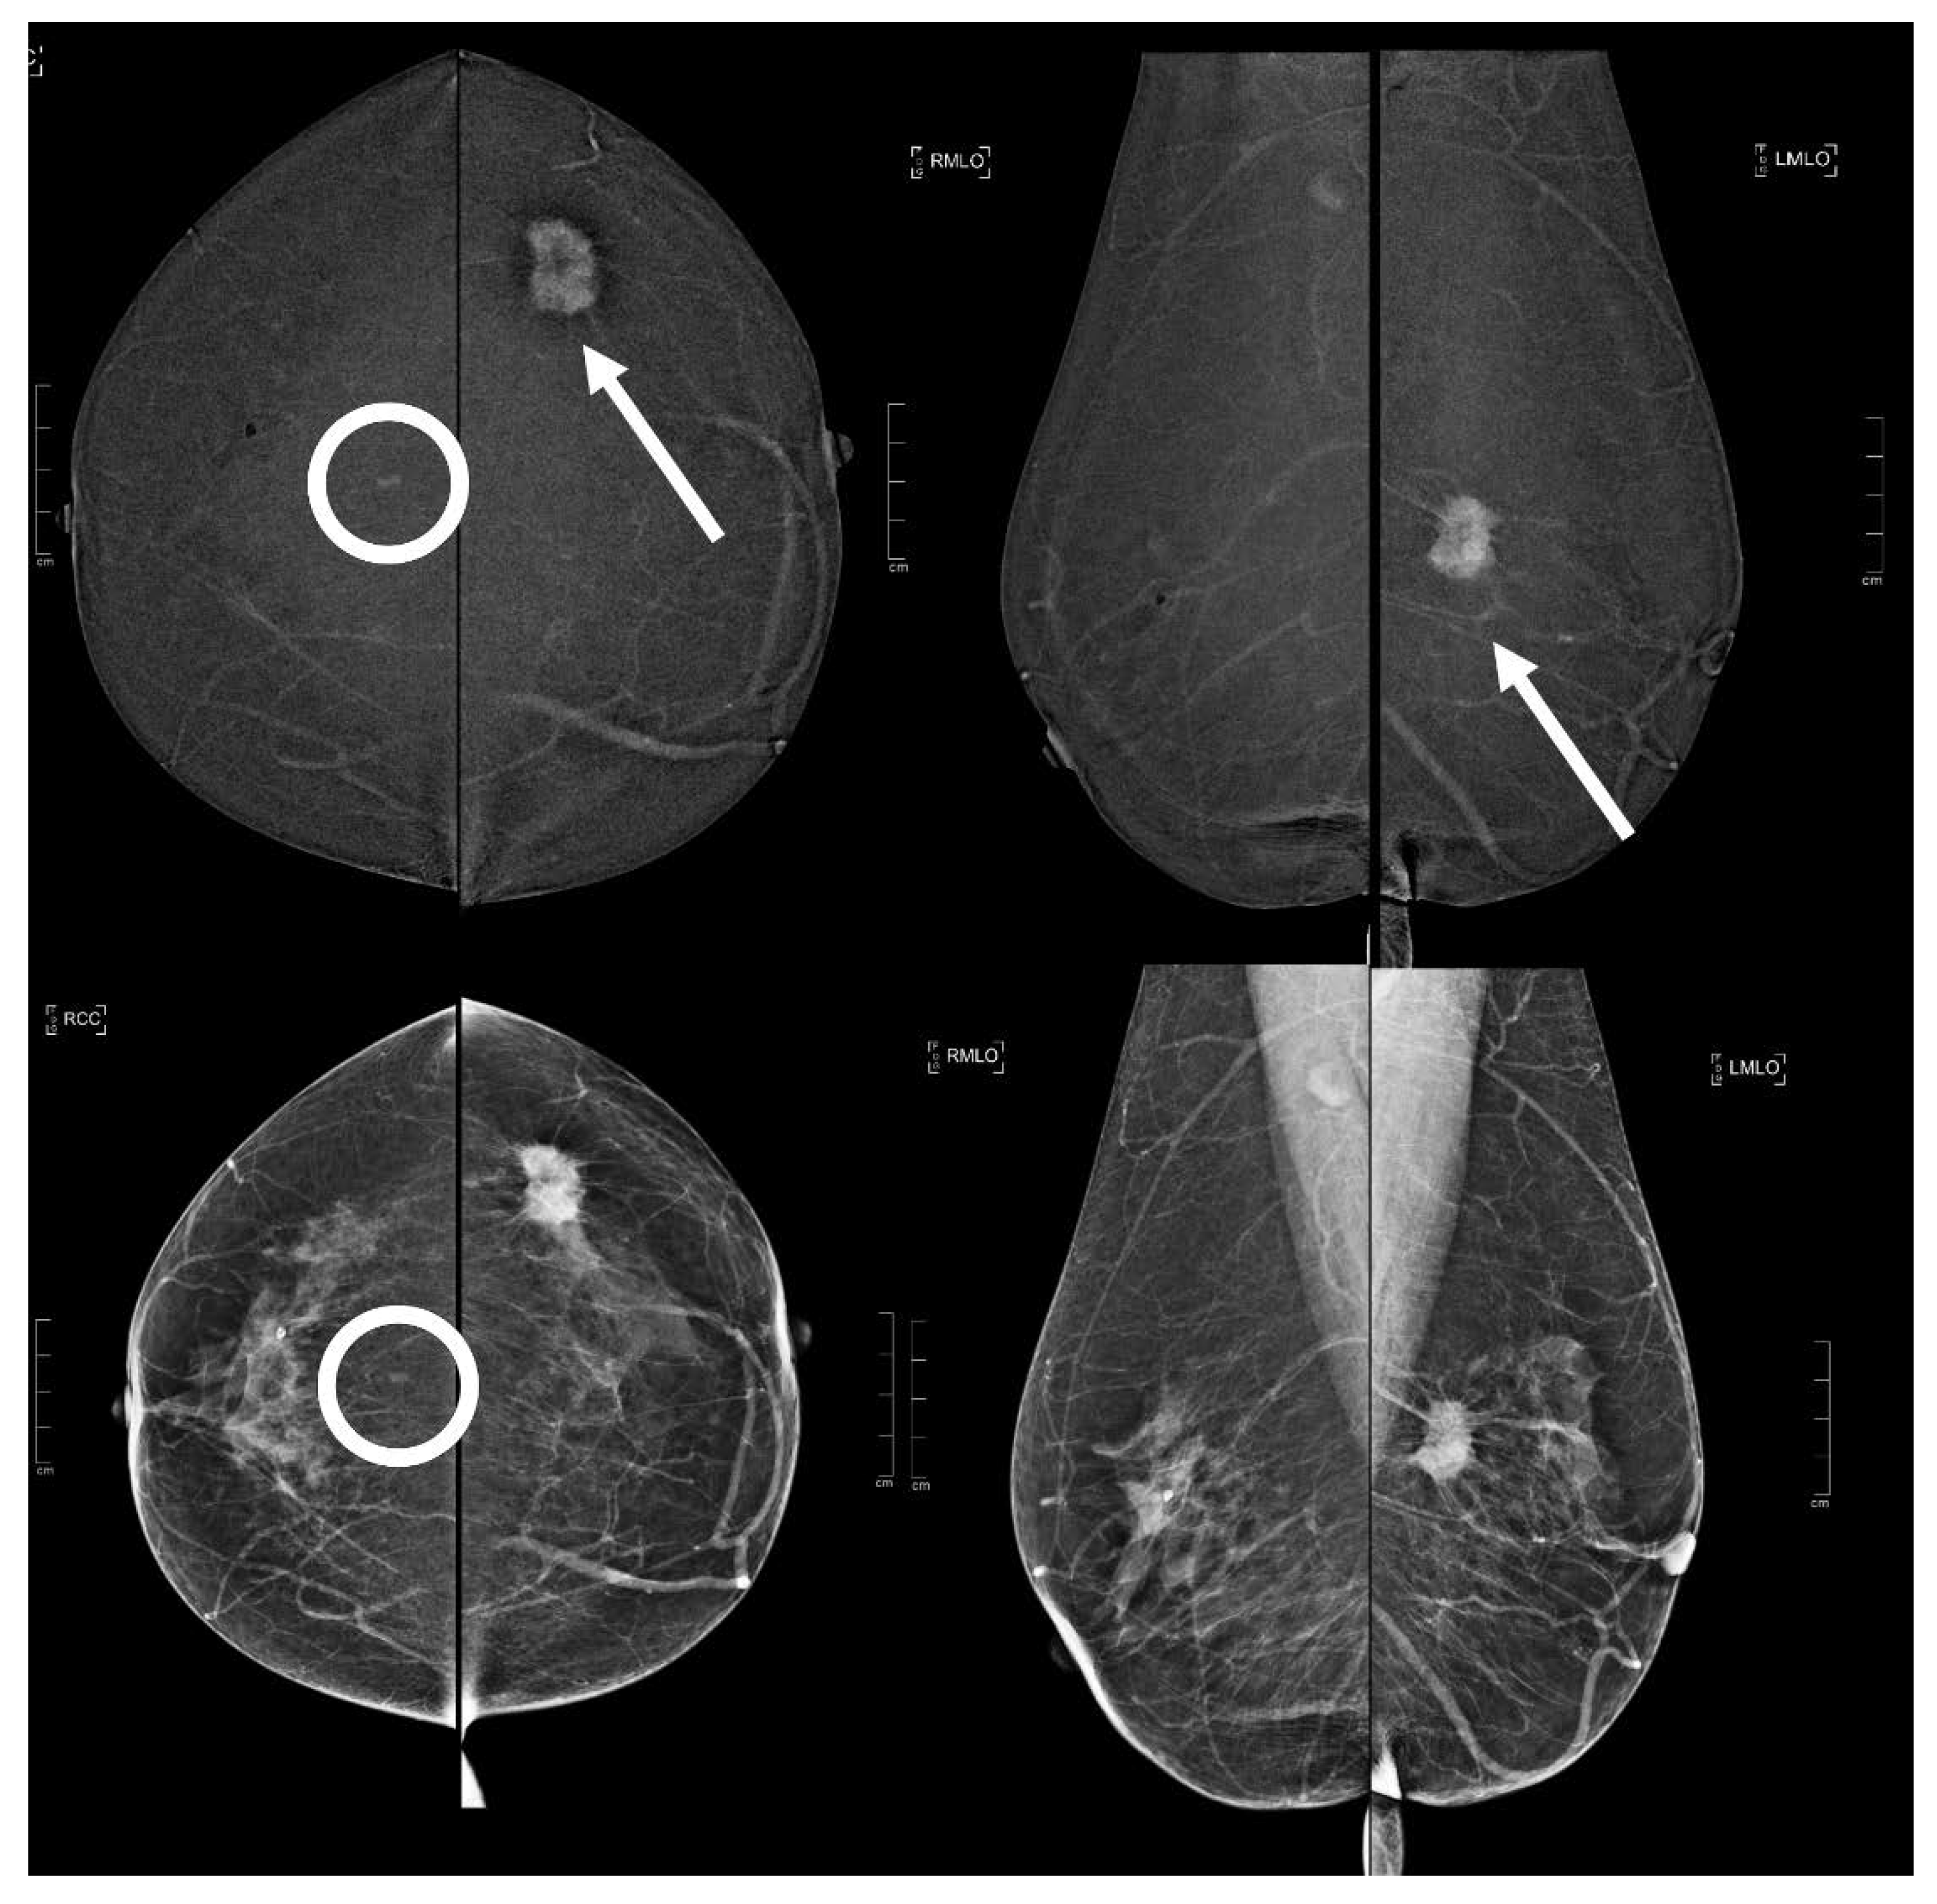

Figure 4.

A 62 year old patient. Contrast-enhanced digital mammography performed as preoperative staging for a B5 lesion in the left breast (arrows). In the early RC in the right breast, there was an enhancing asymmetry in the central quadrants with moderate conspicuity only visible in CC (circle), corresponding to an opacity in low-energy images. This opacity subsequently underwent VABB (tomosynthesis-guided vacuum assisted breast biopsy), which showed a benign lesion (fibrocystic breast change).